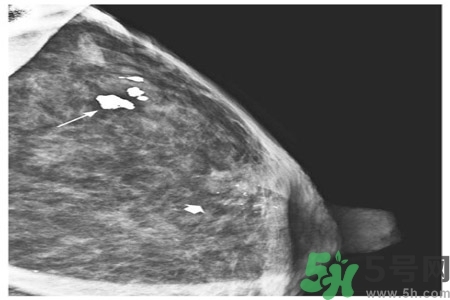

鈣化形態(tài)對辨別病變的良惡性有較大的意義,在觀察中發(fā)現(xiàn)。

顆粒狀、蛋殼狀、不規(guī)則團(tuán)塊狀及軌道狀鈣化多發(fā)生于良性病變。

針尖狀、小桿狀、分叉狀及泥沙樣鈣化多發(fā)生于惡性病變,鈣化的形式多樣、大小差異很大時,惡性的可能性越大,單純出現(xiàn)一種形態(tài)的鈣化時,成簇的針尖狀、分叉狀鈣化,對診斷惡性病變的意義較大。而單純出現(xiàn)泥沙樣鈣化,對病變的良惡性判別則比較困難。泥沙樣鈣化為不確定性鈣化,良惡性有重疊,但如果泥沙樣鈣化伴有其他鈣化形式,提示惡性病變。

乳腺鈣化部位

了解鈣化部位應(yīng)強(qiáng)調(diào)多方位、多角度觀察。良性鈣化灶,多發(fā)生在纖維組織、脂肪、血管、大汗腺、皮膚等乳腺間質(zhì)內(nèi),乳腺實質(zhì)內(nèi)少見。惡性鈣化則多發(fā)生于乳腺實質(zhì)內(nèi),泥沙樣鈣化多發(fā)生在乳腺小葉腺泡內(nèi),小桿狀鈣化多發(fā)生在導(dǎo)管內(nèi),小叉狀鈣化則多位于末支小導(dǎo)管內(nèi)。